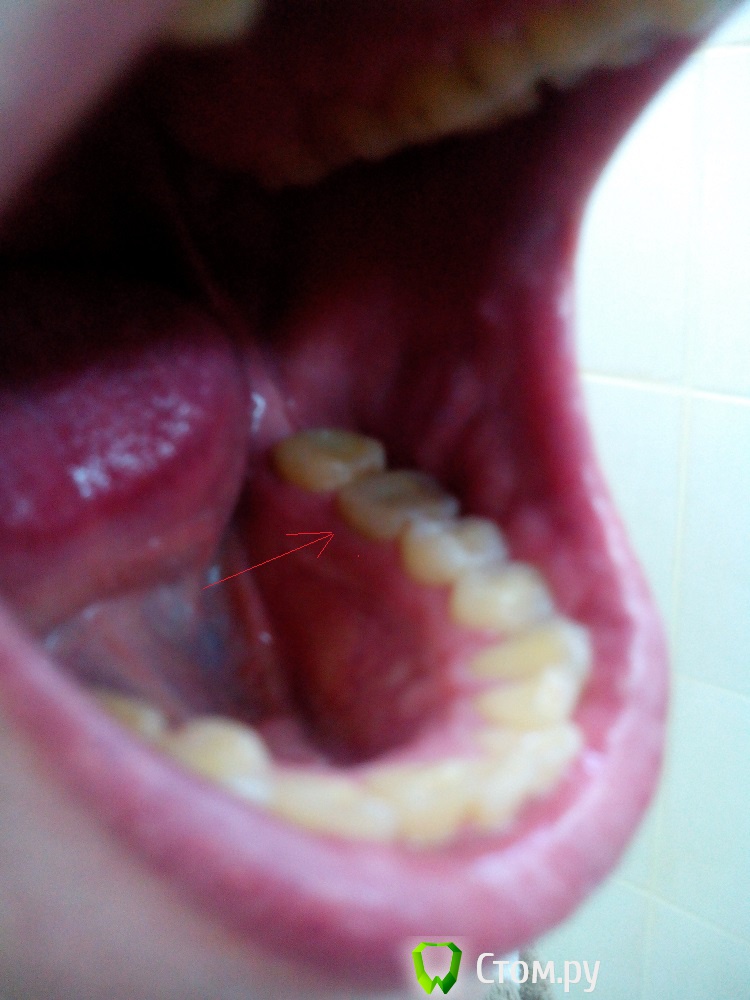

IvanK Опубликовано 16 июня, 2014 Поделиться Опубликовано 16 июня, 2014 Если судить только по снимку - зуб нужно удалять, ввиду сильного разрушения, ниже уровня десны+1 фото бы посмотреть Ссылка на комментарий

edw Опубликовано 16 июня, 2014 Автор Поделиться Опубликовано 16 июня, 2014 пока сфоткал так, как смог Ссылка на комментарий